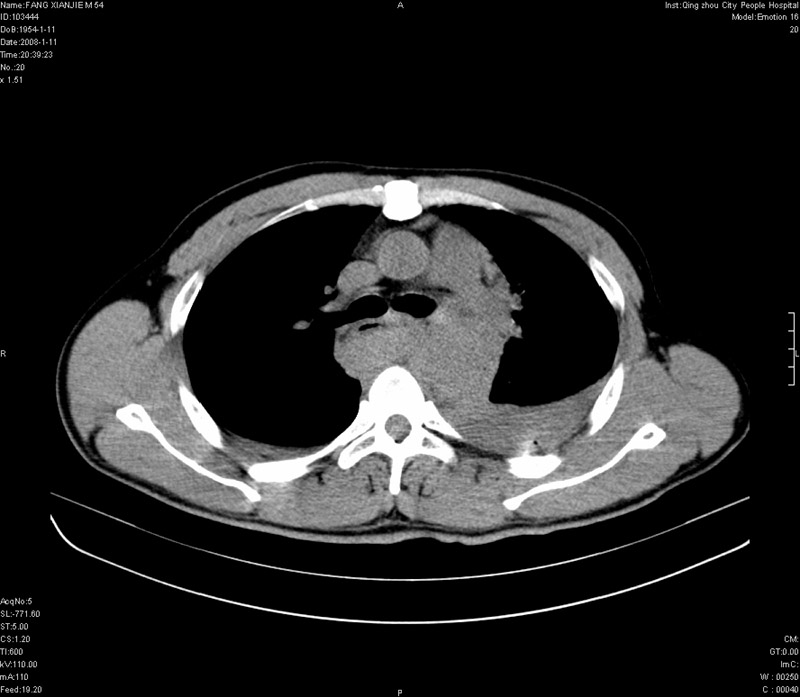

男性,40岁。胸部被车压伤伴胸痛1小时来院就诊。检查:一般情况尚可,血压110/80,胸部及上腹部压痛。结果在三天后公布。骨窗在横断位、冠矢状显示肋骨、胸椎、和胸骨未见骨折征象。

ct11308:胸部外伤1小时(证实病例) (2008-1-13 16:2)结果如下:病人入院后两小时后症状加重,8小时后在征得病人家属同意做了ct增强扫描。如下图。最终临床诊断:外伤性胸主动脉破裂并纵隔内血肿。由于有运动性伪影,胸骨在矢状面重建的图像似有骨折征,这是一种假象,我们称之为“假骨折”,这在多层ct重建中经常性遇到,必要时要结合横断图像鉴别之。现在,病人的一般情况较差,是否要手术家属尚有争议,如果手术修补,难度较大,需要专门预定制作固定支架。

当然,对于该病例,其它非重要的诊断还有:右侧少量气胸;左侧胸腔积液;左侧轻度肺挫裂伤。对于纵隔内血肿,我们曾经遇到过多例,也有怀疑主动脉的破裂,但是,均未得到具体出血部位的明确诊断。